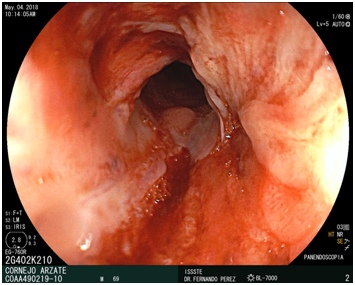

An UGE was performed, with PENTAX Pediatric video endoscope, a stricture of 80% of the lumen was visualized at proximal third esophagus, the length of 1cm, with no pass through of the scope. The final diagnosis was a Complex proximal third esophageal peptic stricture.

The role of surgery in benign stricture is largely limited to ant reflux procedures to manage the GERD that is etiologic in most benign strictures (Figure 1-5).

Figure 2 Proximal third esophageal peptic stricture endoscopic view.

Figure 3 Proximal third esophageal peptic stricture endoscopic view.